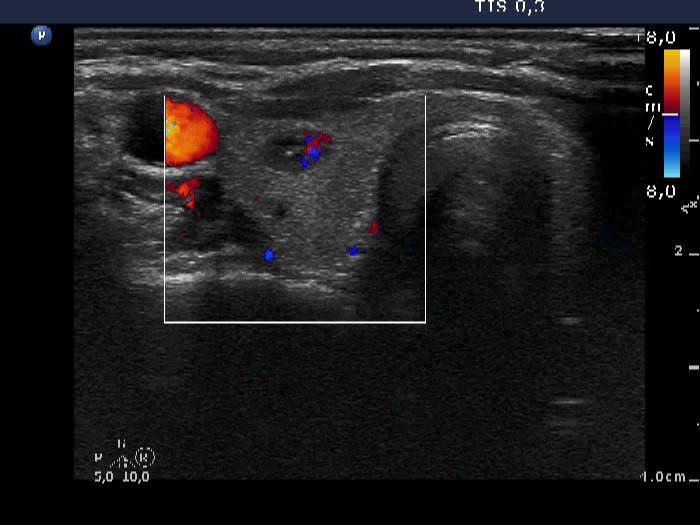

Right lobe, transverse scan, color Doppler mode. The nodule presents intranodular vascularity.